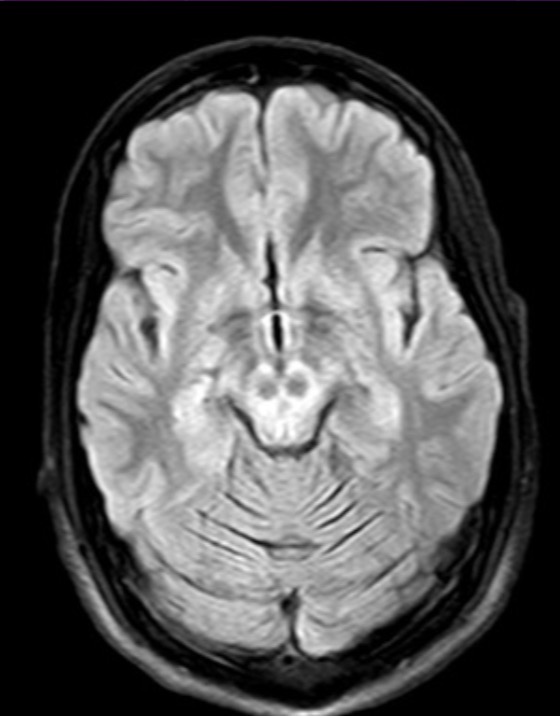

20 year-old female presents with tremor and dystonia

Panda sign = Wilson disease aka hepatolenticular degeneration